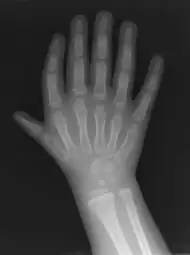

Triphalangeal thumb (TPT) is a congenital malformation where the thumb has three phalanges instead of two. The extra phalangeal bone can vary in size from that of a small pebble to a size comparable to the phalanges in non-thumb digits. The true incidence of the condition is unknown, but is estimated at 1:25,000 live births.[1] In about two-thirds of the patients with triphalangeal thumbs, there is a hereditary component.[2] Besides the three phalanges, there can also be other malformations. It was first described by Columbi in 1559.[3]

The triphalangeal thumb has a different appearance than normal thumbs. The appearance can differ widely; the thumb can be a longer thumb, it can be deviated in the radio-ulnar plane (clinodactyly), or thumb strength can be diminished. In the case of a five-fingered hand it has a finger-like appearance, with the position in the plane of the four fingers, thenar muscle deficiency, and additional length. The flexion and extension can be limited as well.[4]There is often a combination with radial polydactyly.

The diagnosis can be made on a physical examination and on an X-ray.[4]